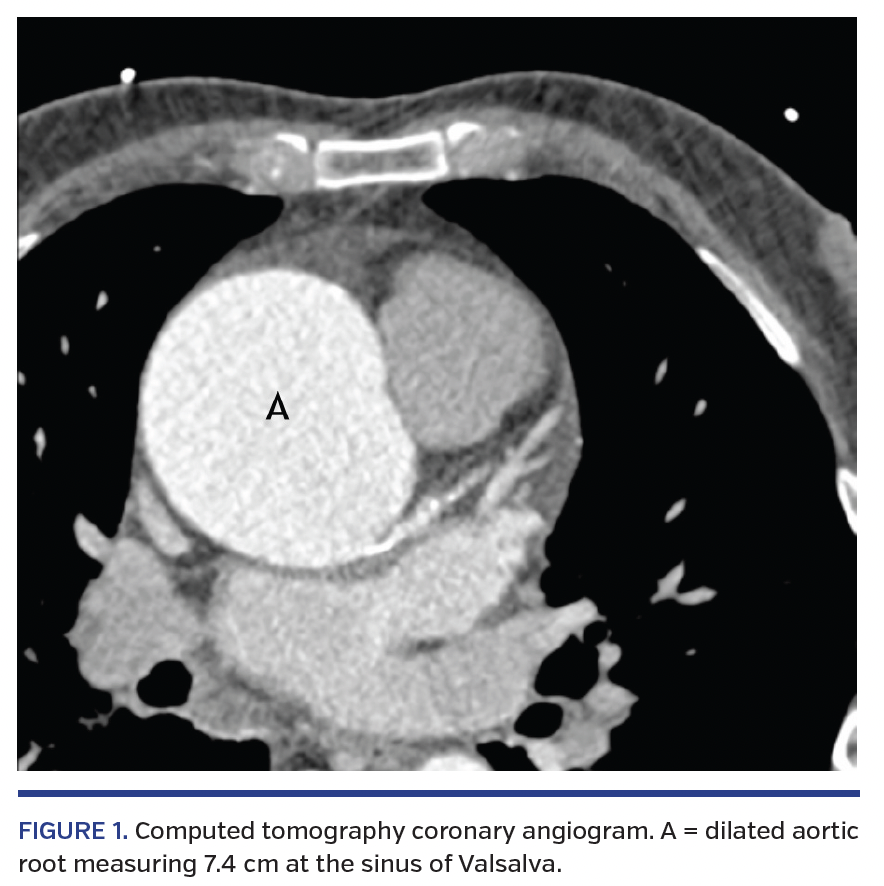

A 76-year-old male with a history of hypertension, dyslipidemia, smoking, and a family history of coronary artery disease presented to his local hospital following a non-ST segment elevation myocardial infarction. Selective coronary angiography was unsuccessful due to a severely dilated aneurysmal aortic root and associated aortic valve regurgitation, despite the use of the following catheters: Tiger 4.0; Judkins left 4, 5, 6; EBU 6.0; Amplatz left 1, 2, 3; MPB, and Judkins right 4.0. The patient was referred to our tertiary center for computed tomography (CT) aorta and coronary angiography. CT aorta demonstrated aortic dilatation of 7.4 cm just beyond the sinotubular junction (Figure 1), with slight displacement of the coronary ostia secondary to the marked aneurysmal dilatation. CT coronary angiography was inconclusive; it reported severe calcification in the left main stem (LMS) with concern of flow-limiting disease, a likely 70% stenosis in the mid right coronary artery (RCA), and indeterminate findings in the left anterior descending (LAD) and circumflex (LCX) arteries due to calcification. Echocardiography reported moderate-severe aortic regurgitation, with preserved left ventricular systolic function.